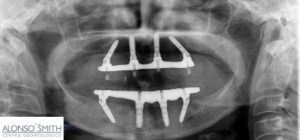

La técnica All-on-Four aprovecha el hueso denso que permanece en la parte frontal de los maxilares (superior e inferior) y colocando los dos implantes posteriores en ángulo para evitar las cavidades sinusales en el maxilar superior y el canal nervioso en el maxilar inferior.

Este procedimiento ha eliminado prácticamente la necesidad de un injerto óseo costoso, junto con la incomodidad y el tiempo de cicatrización prolongado que a menudo acompaña estos procedimientos adicionales. Hoy en día, gracias a la técnica All-on-Four, es posible que los pacientes tengan un dentadura fija colocado el mismo día en que reciben sus implantes y casi siempre sin necesidad de injerto óseo.

En el pasado los especialistas considerábamos que eran necesarios entre 6 y 10 implantes para suministrar suficiente estabilidad a una rehabilitación con implantes fija de arco completo. La nueva tecnología ha encontrado que si los implantes finales se colocan con una determinada angulación, su fuerza se incrementa drásticamente. Esto nos permite ser capaz de anclar un puente fijo con tan sólo 4 o 6 implantes – mucho menos de lo que se utiliza normalmente. Colocar menos implantes también ahorra mucho dinero. Además, los implantes y los nuevos dientes se colocarán en la misma visita

El All on Four posibilita la colocación de todas la piezas fijas de una boca por un precio significativamente menor que con otras técnicas. Ello es posible por que este procedimiento utiliza sólo 4 implantes para reemplazar todos los dientes en un arco, mientras que las técnicas tradicionales utilizan entre 5 y 8 implantes en un arco. La colocación en ángulo de los implantes posteriores del procedimiento All-On-4 permite un mayor soporte usando el soporte natural de su hueso. Además, los implantes tradicionales a menudo requieren el injerto óseo, un proceso que puede tardar 6 meses o más. El protocolo All-On-4 no requiere injerto óseo para la mayoría de los pacientes, con una tasa de éxito igual o mejor que los implantes tradicionales.